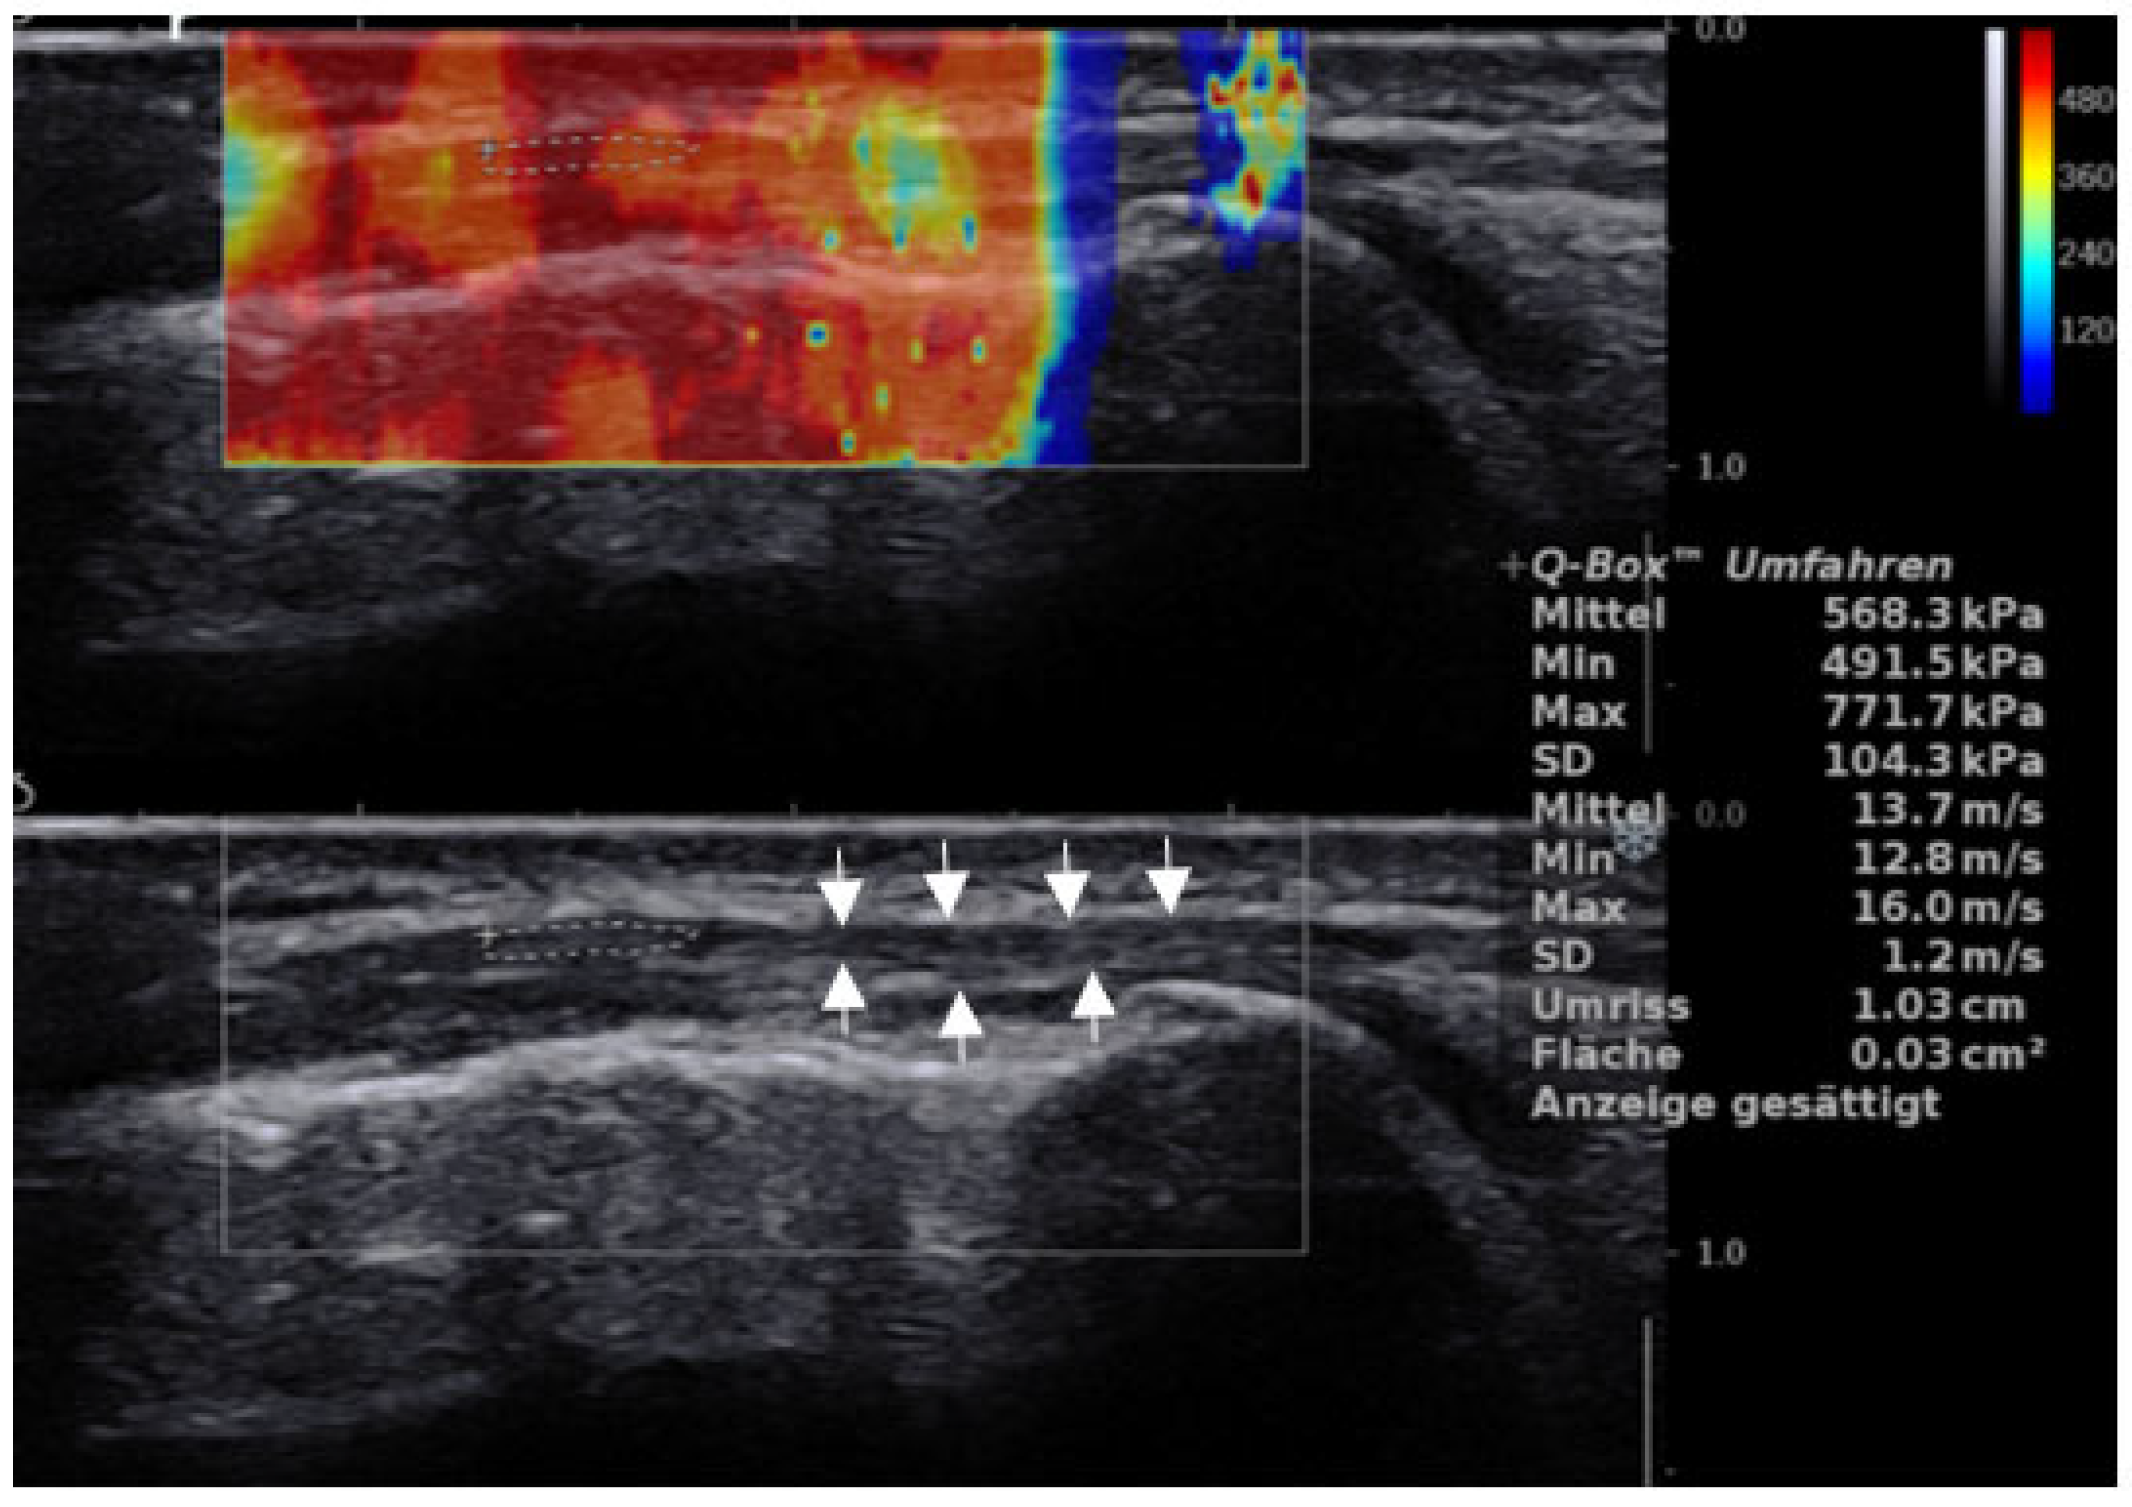

2.2. US Examination

3.1. ITB